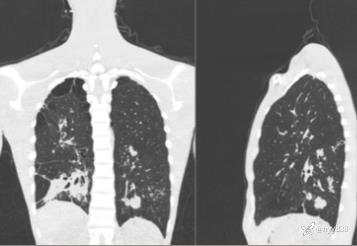

性别:男

年龄:38岁

简要病史:慢性声音嘶哑,最近体重减轻。

实验室检查:白细胞稍高,HPV阳性

体查:吸气喘鸣

胸部CT平扫